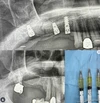

İmplant

Sinüs Lifting

Kemik Greftleme

İmplant Üstü Protezler